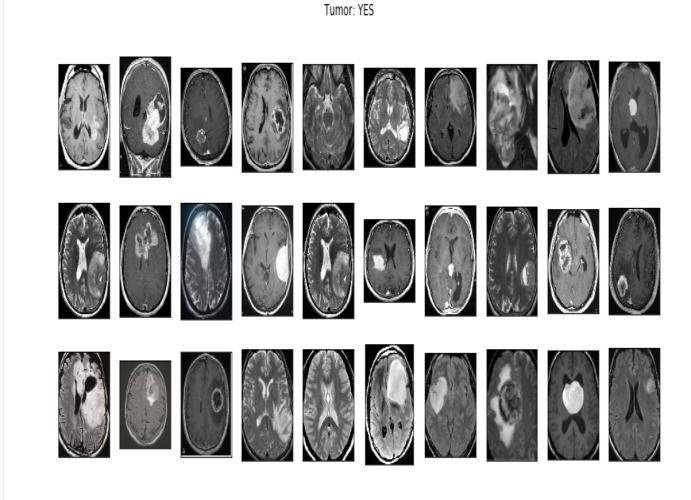

Thedatasetconsistedof708meningiomapositiveimages, 1426 glioma tumor images and 930 pituitary tumor images.

We use three separate segmentation tasks to show the u net in action. The segmentation of neural structures in recordings made using an electron microscope is the first challenge. We employed a brain tumor segment dataset for this experiment, which is accessible online. 3064 MRI scans and 3064 masks are included. A collection of 30 images serially sized 512x512 section which transmits throughelectronmicroscopyoftheventralnervecordofa Drosophila serves as the training data (VNC). To proceed with the implementation and classification, the ground truth data which is completely tagged for each image is consideredforthewhiteandbackmatteroftheimages.U netmodelhasbeenchosenfortheexperimentationasthis model does not need any further processing either before or after diagnosis which internally makes the model less pronefortheerrorsandaswellensurethatitoutperforms otherclassifierswhichmayneedtobetrainedwithstrong featuremapsaftercarefulprocessingofthedata.However theU netmodelalsosuffersawarpandrandomerror.

TrainandValdatasetsareseparatedinthetrainingfolder. Four groups of tumour MRIs are contained in each folder. The epoch rate was set to 50. The dataset file is then unzippedandsavedinapredeterminedpathandfolder.A dictionary is explained in relation to data visualisation. Our four classes ('glioma tumor,' "no tumor," "meningioma," and "pituitary tumor") are the dictionary keys. A directory of images is present in each row. The number of photos in each class in the training and testing sets is then counted using an initialised list. We print the total number of photos in each class for the train and test sets.